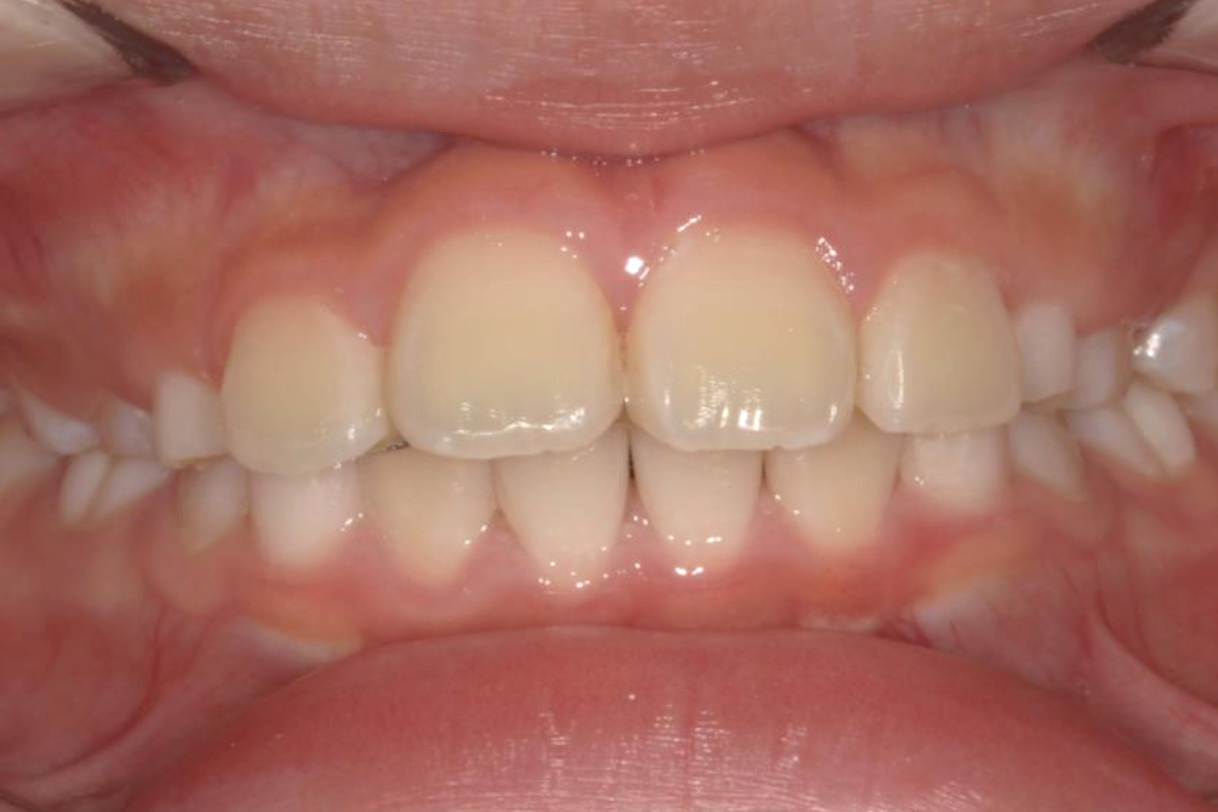

初診時年齢:7歳

治療:前歯部矯正

治療法:上顎前歯部表側の装置

治療期間:2ヶ月

費用:110,000円(税込)

リスク・副作用:装置装着による違和感、歯の移動時の痛み